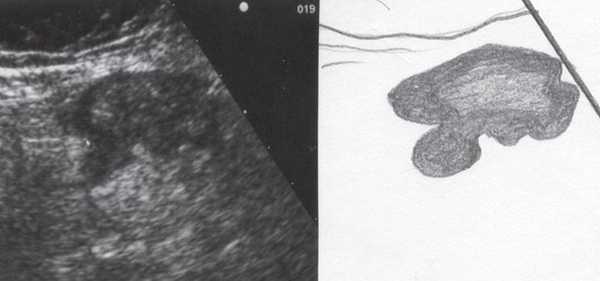

При трансвагинальном УЗИ (рис. 4) также визуализировался фрагмент толстой кишки с утолщенными гипоэхогенными стенками и несколькими округлыми дивертикулами до 1 см в диаметре. Контуры одного из дивертикулов были неровными, он имел звездчатую форму. Отмечались утолщение и повышение эхогенности околокишечной жировой клетчатки по сравнению с контралатеральной стороной. При осмотре в режиме УЗ ангиографии утолщенная стенка кишки и дивертикулы были аваскулярными, окружающая клетчатка - гиперваскулярной.

Рис. 4. Эхографическая картина дивертикулита. Трансвагинальное исследование конвексным датчиком 7,5 МГц.

В приведенном наблюдении при УЗИ визуализировались множественные выпячивания истонченной кишечной стенки. На участках утолщенной стенки между дивертикулами и в самих дивертикулах сосудистый рисунок был обеднен или не визуализировался, что подтверждает роль сосудистого фактора в развитии болезни: сдавление внутристеночных сосудов с нарушением микроциркуляции, наличие ишемии и замедления венозного оттока. Некоторые дивертикулы были заполнены гомогенным аваскулярным содержимым средней эхогенности, без признаков внутрипросветного движения, так что содержимое сливалось с изображением стенки. В других дивертикулах пузырьки газа, выступая в качестве естественного контраста, позволили детально рассмотреть истонченную до 0,9-1,1 мм стенку кишки, лишенную гипоэхогенного мышечного слоя. Форма этих дивертикулов приближалась к шаровидной, устье было меньше, чем диаметр дивертикула. Однако встречались и выпячивания в форме конусов, с устьями, превышающими размеры самого дивертикула, в них прослеживалось продолжение гипоэхогенного мышечного слоя стенки.

Очевидно, эта разница в ультразвуковом изображении дивертикулов отражает стадии их формирования: округлые с истонченной стенкой и отсутствием в ней мышечного слоя - это сформированные дивертикулы, в то время как другие, в которых еще прослеживается мышечный слой или его фрагменты, - дивертикулы на стадии формирования.